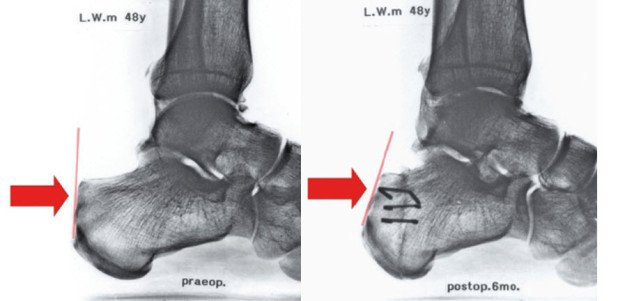

Verklebungen der Sehne zum Fersenbein sind mitverantwortlich für lange, unbefriedigende postoperative Verläufe. Seit über 10 Jahren verwenden wir deshalb an der Schulthess Klinik eine andere Operationstechnik für die Behandlung der Haglund-Ferse. Das Prinzip dieser Operation ist eine «indirekte» Entfernung des Überbeins, die den störenden Knochen von der Achillessehne wegklappt. Das Überbein verschwindet, die Gleitschicht bleibt aber erhalten. Die Sehne und die chronische Schleimbeutelentzündung können sich erholen.

Durch die «indirekte» Resektion wird die empfindliche Stelle an der Ferse mit ihrer Gleitschicht gar nicht berührt und bleibt intakt. Dieses Operationsverfahren wurde bereits vor vielen Jahren erstmals beschrieben, gelangte jedoch zunehmend in Vergessenheit. Wir entdeckten das Verfahren sozusagen neu und wendeten es zunächst nur bei der klassischen Haglund-Ferse an, die keine sichtbaren Veränderungen an der Achillessehne zeigt. Ermutigt durch die guten Erfolge begannen wir das Operationsverfahren auch bei Fällen mit begleitender Sehnendegeneration anzuwenden. Die Operation wird in einer auf den Fuss beschränkten Narkose durchgeführt.